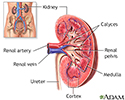

Kidney anatomy - illustration

Kidney anatomy

illustration